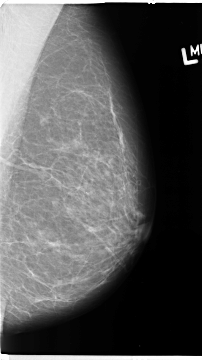

B_3121_1.LEFT_MLO

LEFT_MLO LINES 4672 PIXELS_PER_LINE 2616 BITS_PER_PIXEL 12 RESOLUTION 50 NON_OVERLAY